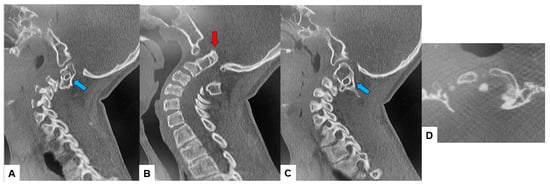

2.3. Preoperative Imaging